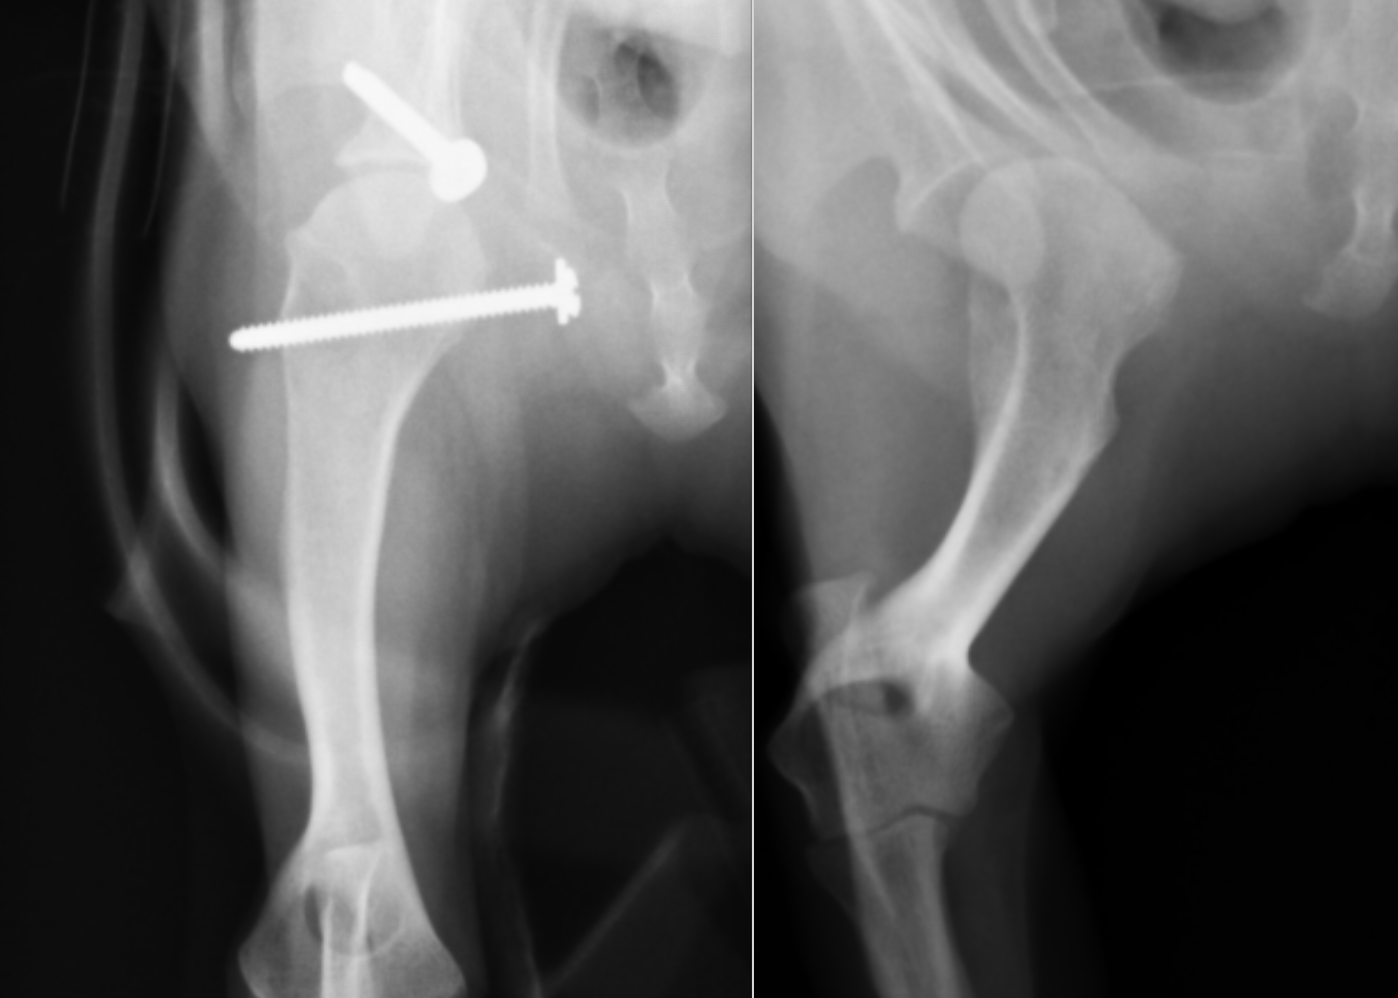

別の症例です。右が術前、左が術後のレントゲンです。分かりやすく肩甲骨と上腕骨に線を引くと・・・・

オレンジのラインが肩甲骨で、赤いラインが上腕骨頭です。右の術前は全くあっていなかった関節が、左の術後にはピッタリとあっているのがわかると思います。今回は前回のスクリューにプラスして、肩甲骨にもアンカーを入れ、糸による靭帯の強化をおこなっています。

横から見たレントゲンです。右が術前、左が術後です。こちらも線を引くと

右のレントゲンではオレンジと赤のラインが全く合っていなかったのが、左の術後ではピッタリとあっているのがわかると思います。